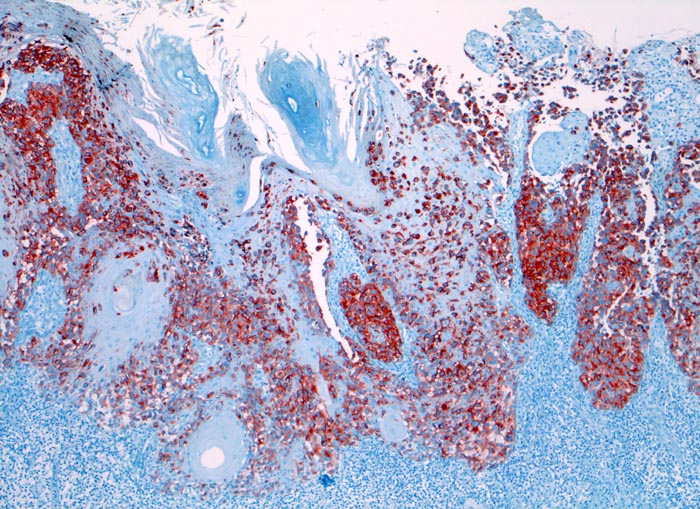

amelanotisches akral lentiginöses Melanom

Haut, Hand palmar, Finger

Die Melanomzellen färben sich an mit dem Melanommarker HMB-45. Dabei wird die Ausdehung der Tumorzellinfiltrate deutlich. An der Oberfläche sind die Zellen diskohäsiv.

Makroskopisch ulzerierte Läsion mit hellbraunem Grund.

HMB-45